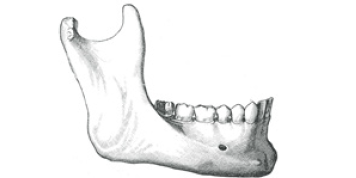

Figure 1: Mandible illustrating sub-periosteal implant. From: Types of Dental Implants, http://www. dentalimplancostguide.com/types-of-dental-implants/

Today’s dental implants can be categorized by their shape and placement as well as by the procedure used to place them, e.g. single or two-staged. The implant can be ‘buried” under the soft tissue or left above the tissue. If the implant is left under the tissue as a first stage, the second stage would be to uncover it by means of a scalpel or laser, remove the healing screw and place a healing cuff of specific height above the gingiva that will, in time, contour the gingiva with a flare or specific “immersion profile,” while healing. The final stage would be to place the abutment head and take an impression for the subsequent crown. The following Figures 1-4 [4] illustrate types of implants, nomenclature of implants based on materials and surface coating as well as placement of the different implants.

Sub-periosteal implants have been commonly used for single and two stage procedures in the past. They are positioned inside the gum tissue on the jawbone. The post protrudes from the gums to hold the restoration. The primary advantage of this type of implant is that it can hold dentures securely for individuals who do not have enough bone height. This procedure can be accomplished in a two-stage surgical procedure; one exposing the bone and taking an impression and two, exposing the bone a second time and placing the implant under the periosteum after it has been fabricated by a dental laboratory. More modern technology allows for a CAT scan (Computerized Axial Tomography) of the jawbone with a resultant three-dimensional model that can be used for fabricating the implant itself. Thus, a one stage placement can be made reducing the stress of having two surgeries, discomfort, and inconvenience. Older individuals who opt for this procedure should be limited to the one stage technique, if possible, due to fragility and deleterious side-effects. The Endosteal dental implants are the most used implants today, especially for two-stage procedures. They are a good alternative to bridges or detachable dentures; however, they can be used to support over-dentures in a very effective way using implant bar support, locator attachment’s as well as a large number of other attachments. These implants come in several types including screw/threaded, cylinder/smooth and bladed. The cylindrical and tapered screw implants are usually coated and/or acid-etched for better osseous integration. These implants come in mini and standard sized diameters and lengths.

Bones consist of cells embedded in a mineralized matrix with collagen fibers. The primary tissue of bone is made mostly of calcium phosphate or calcium hydroxyl-apatite. The outer surface of the bone, especially of the face and jaw, is made up of cortical or hard bone. The internal surface of the bone is soft medullary bone or cancellous bone. Both the inferior border of the mandible and the superior surface of the mandible are formed of dense cortical bone. However, when teeth are lost, this bone disintegrates, and the height of the mandible is lowered as in older individuals who have lost their teeth later in life (Figures 5 & 6) [5].

Figure 5: Adult mandible with teeth. From: Gray’s Anatomy.

Figure 6: Edentulous mandible of old age with bone Resorption. From: Gray’s Anatomy.

Without the appropriate bone, both in height and width, implant therapy for most patients is limited. The older one gets, the more prone he or she is to diminished bone presence in one form or another. The mandible is a good indicator of bone loss and with associated tooth loss, bone loss is accelerated.